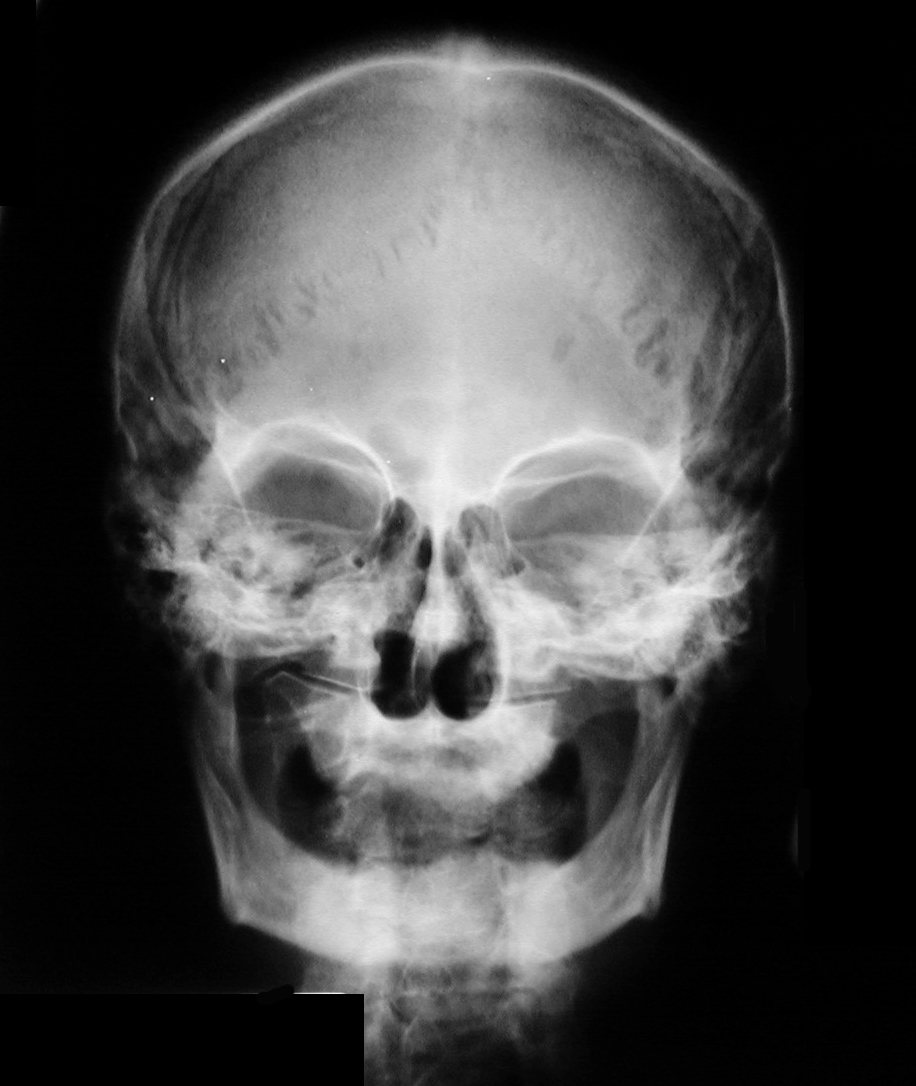

Identify the sutures seen. Click the image for labeling.